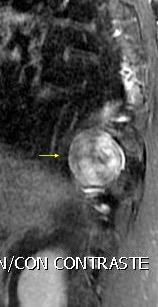

Edad: 40-50 años

3% segregan catecolaminas.

(En el área Paravertebral +/-50%.)

Intenso realce con el contraste.

32 años .Preeclampsia a los 19. Hipertensión no controlada. Masa paravertebral sólida que se realza intensamente con afectación ósea.

Yue Y t al. Asymptomatic left posterior mediastinal functional Paraganglioma. A case report. Medicine . 2019